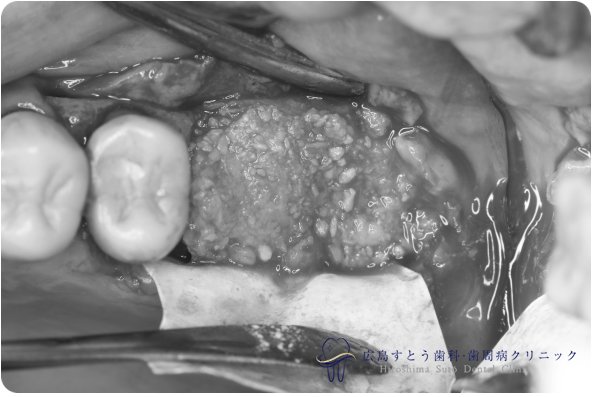

術中

抜歯後の状態

手術中の写真

手術直後のレントゲン

6ヶ月後のレントゲン写真

インプラント手術時

インプラント手術中

| 治療名 | GBR(骨再生誘導療法)、インプラント治療(2本分) |

|---|---|

| 治療説明 | 左上の奥歯に歯茎の腫れがあり、診査の結果歯根が破折しておりました。抜歯後はインプラント治療を希望されたため、抜歯後、失われた歯槽骨を増生するためにGBRを行い、インプラント治療を行いました。 |

| 治療回数・期間 | 約10ヶ月(歯周基本治療、抜歯、GBR、インプラント治療) |

| 副作用とリスク | 歯周外科後には一時的に術後に腫れや仏痛や出血が発現することがあります。 治癒の状態によって治療期間が長くかかる場合があります。 |

| 料金 | 104.5万円 |